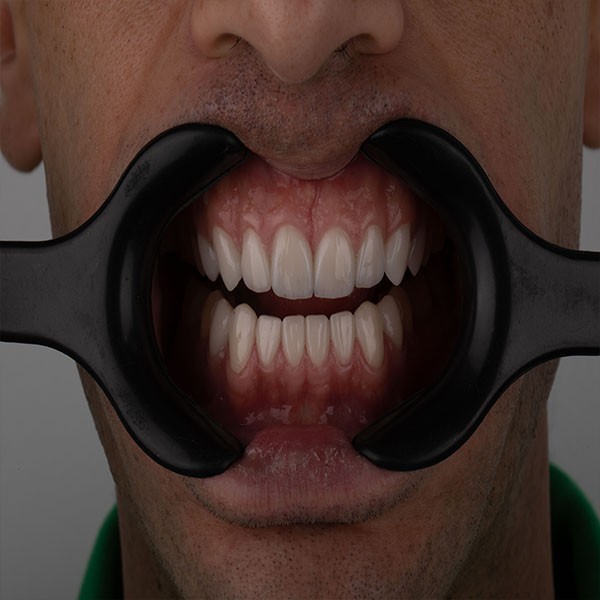

Founded in 2012, our clinic has over a decade of trusted experience in delivering world-class dental care. We specialize in full mouth rehabilitation and implantology, while also offering comprehensive services across all dental specialties including fixed and removable prosthodontics, restorative, endodontics, periodontics, maxillofacial surgery, orthodontics, and pediatric dentistry. Our strength lies in our dedicated team of highly skilled dentists, each bringing diverse expertise, working together with a shared passion for teamwork to ensure every patient receives a personalized care. Equipped with a state-of-the-art CAD/CAM lab, in-house CBCT, and panoramic X-ray technology, we provide a seamless workflow and the convenience of same-day crown deliveries. Our commitment is to combine expertise, precision, and the latest innovations in modern dentistry to create healthy, confident smiles in a professional and welcoming environment.